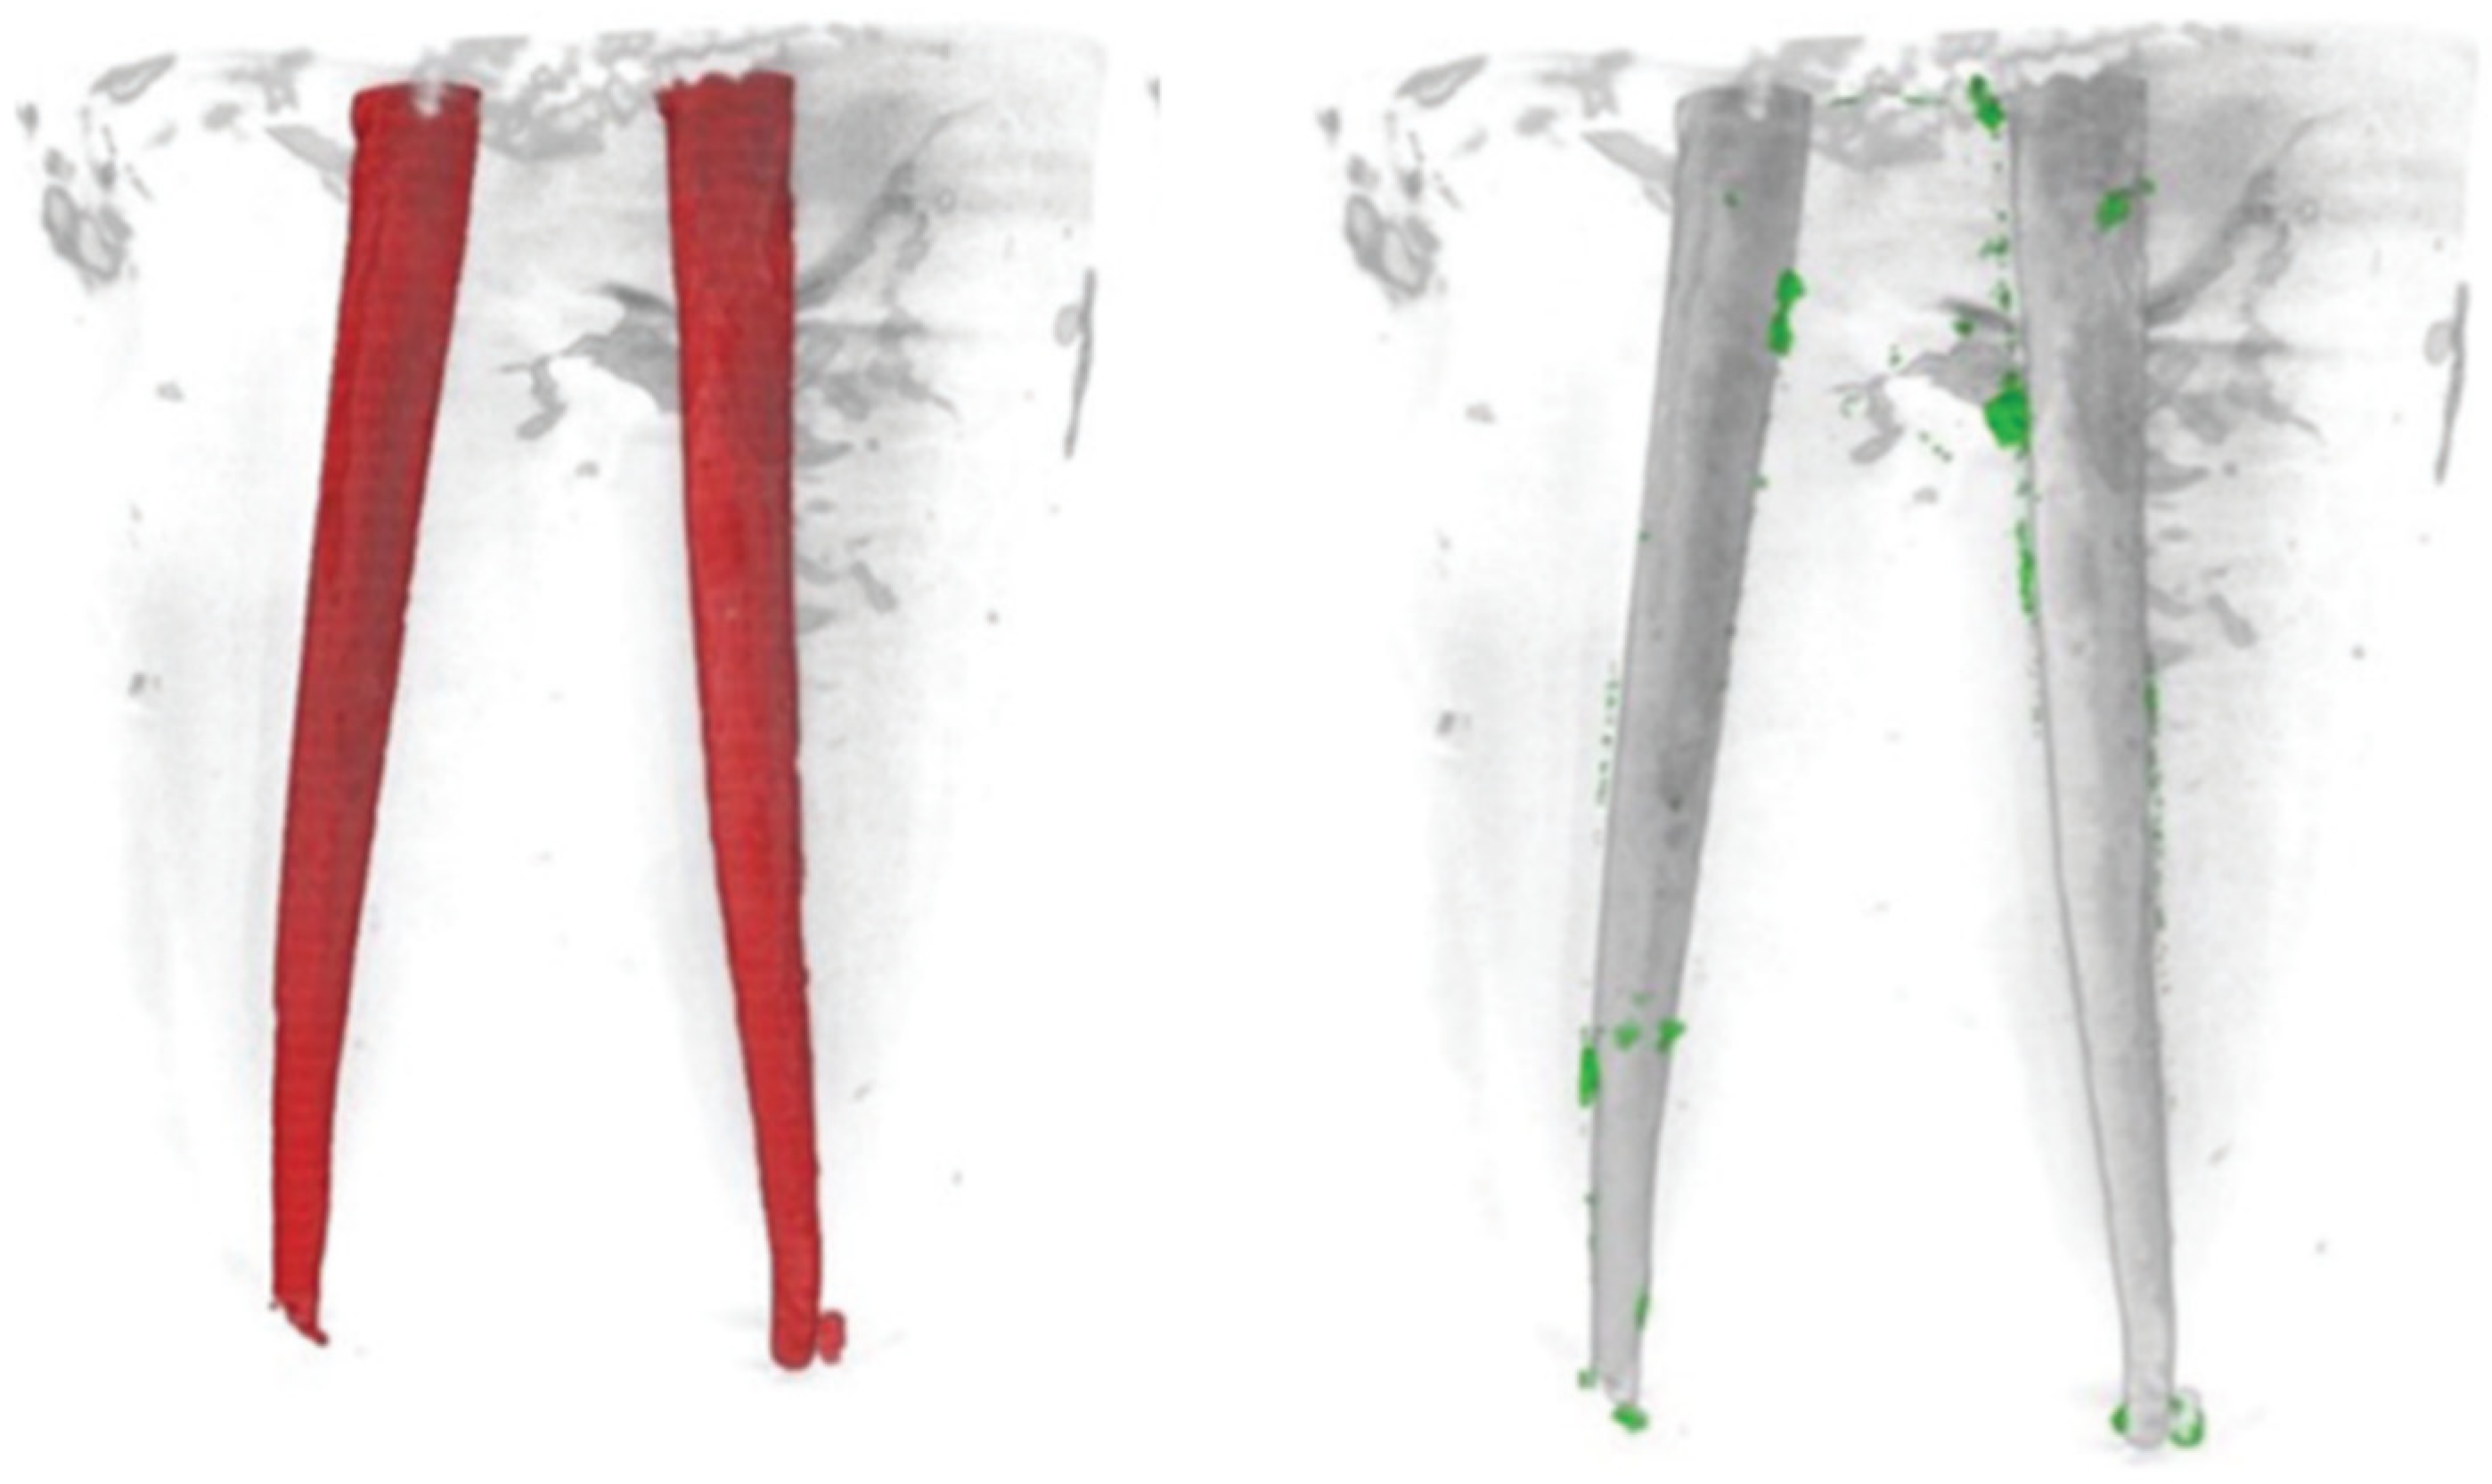

3. Results